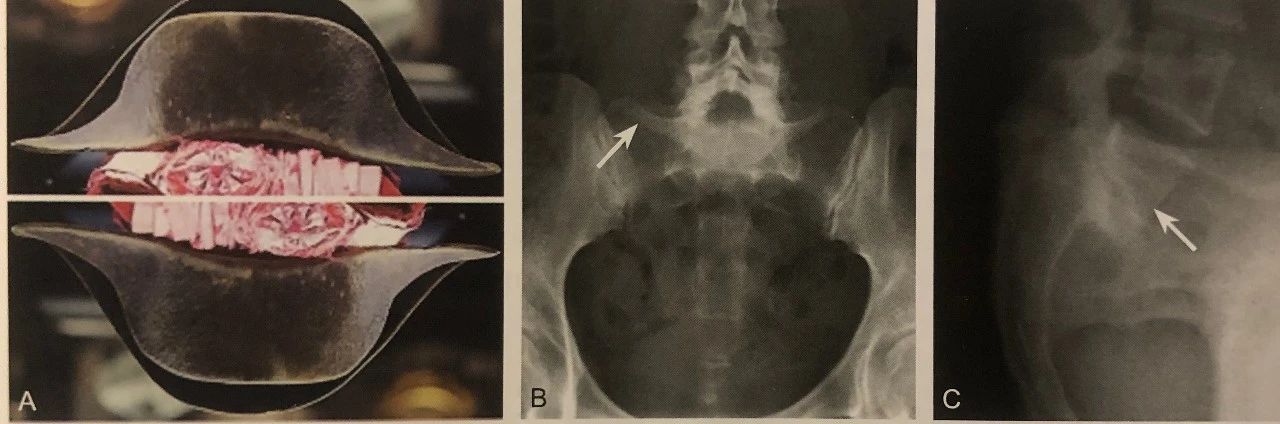

倒 拿 破 仑 帽 征

A.拿破仑帽及倒拿破仑帽;B.倒拿破仑帽征,重叠在骶骨上的L5椎体形成帽的“圆顶”,横突形成帽渐缩的“边缘”(箭头);C.腰椎侧位片显示 L5 椎体Ⅲ°前滑脱(箭头)

判读要点:

1、L5 椎体严重前滑脱的间接征象;

2、在腰椎正位片或腹部、骨盆正位片上观察;

3、出现倒拿破仑帽征时拍摄腰椎侧位片明确诊断;

4、CT 及 MRI 观察椎体、椎管、神经根和周围软组织改变。